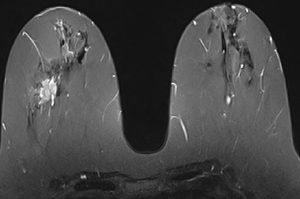

МР-диагностика новообразований молочных желез

- Диагностика и стадирование рака молочной железы